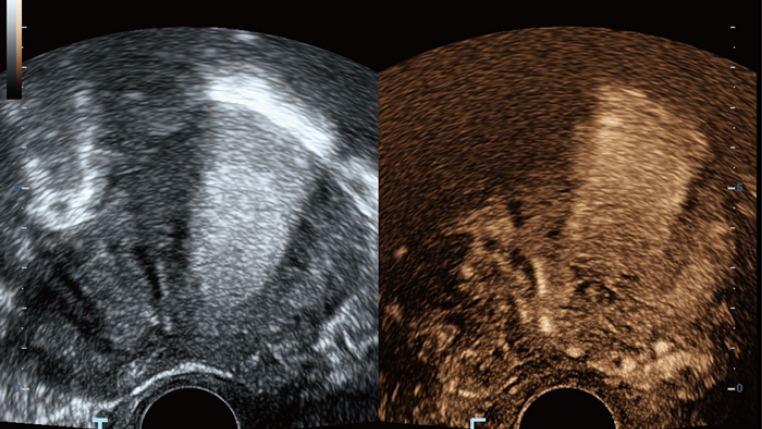

Thanks to the innovative, software-driven ZST+ platform, the Resona series is continuously evolving with the leading-edge technologies to meet the most challenging diagnostic demands in womenŌĆÖs health practice. More importantly, it is designed with the understanding that the wisdom of experts is always precious, and you need more intelligent partner for enhanced speed and confidence. Finally, Resona series with Zone Intelligence provides a total solution to help you with diagnostic confidence, efficiency, and standardization across different diagnostic challenges in todayŌĆÖs demanding and overburden hospital environment.

Advanced Features